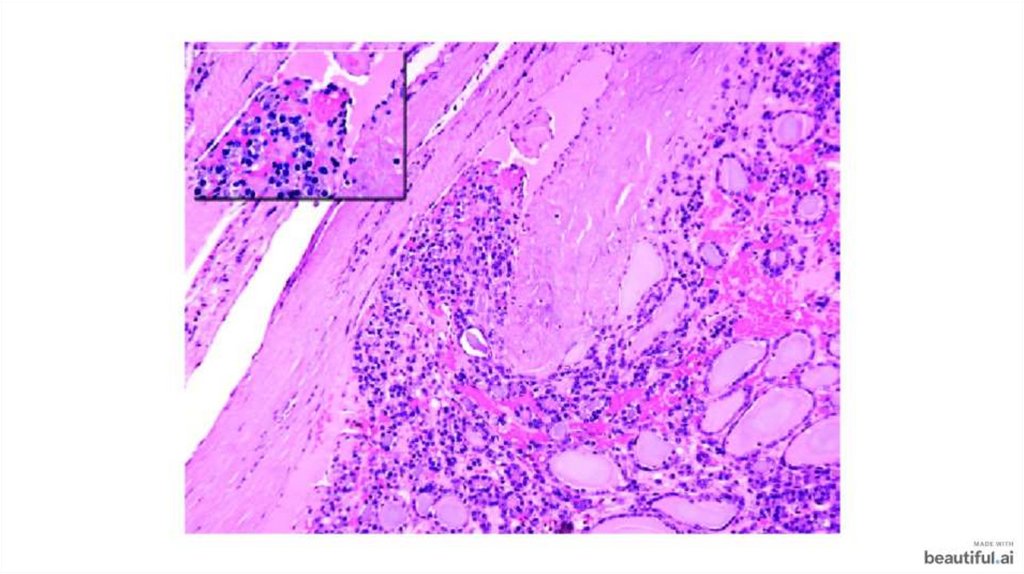

Фолликулярный и папиллярный рак щитовидной железы